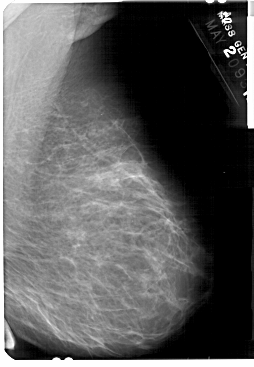

A_1369_1.RIGHT_MLO

RIGHT_MLO LINES 5491 PIXELS_PER_LINE 3796 BITS_PER_PIXEL 12 RESOLUTION 43.5 NON_OVERLAY